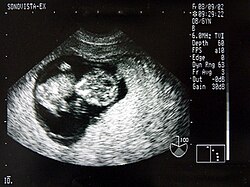

Neben der Herztonwehenschreibung (Kardiotokografie) ist sie ein Standardverfahren in der Schwangerschaftsvorsorge. Eine spezielle Untersuchung der Pränataldiagnostik zur Erkennung von Entwicklungsstörungen und körperlichen Besonderheiten ist der Feinultraschall.

Von den Monitorbildern werden zur Dokumentation Ausdrucke, sogenannte Sonogramme, oder gelegentlich Videoaufnahmen gemacht. Schwangeren wird häufig auch ein Bild ihres ungeborenen Kindes überlassen.